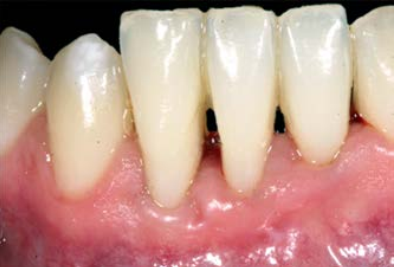

Figure 4 Recipient site five months after surgery. The MIE- FGG is completely blended, achieving an esthetical result. Although GR still remains the phenotype is thickened.

It was determined that gaining was 1 mm for both, width and height; the esthetical outcome was assessed together with the patient, who reported being satisfied with the appearance of the graft and having had no postoperative complications or pain.

Only 14 days after surgery the donor site did appear to be completely healed (Figure 3C) and after five months the graft placed at the recipient site seemed to be well blended with the surrounding gingival tissue (Figure 4) maintaining the width and height gained.